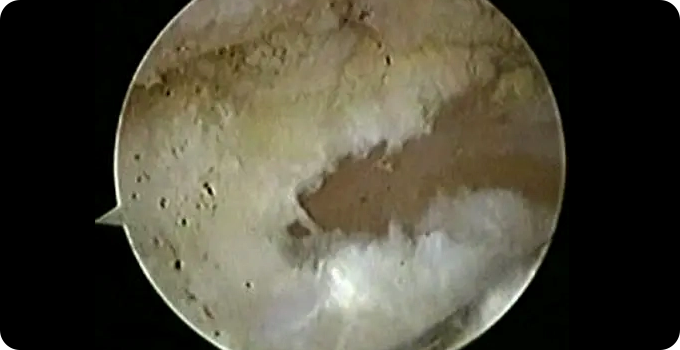

최소절개 관절내시경

족저근막염의 관절 내시경 치료는 최소 침습적 방법으로 족저근막의 염증과 손상을 치료하는 수술입니다. 관절내시경을 사용하여 작은 절개를 통해 근막의 상태를 실시간으로 확인하며, 비후된 근막을 부분 절개하거나 늘려주는 유리술을 진행합니다. 이 치료는 수술 시간이 짧고 흉터가 적으며, 빠른 회복과 일상 복귀가 가능하다는 장점이 있습니다.

• 내시경적

치료

• 5mm 이하의

최소절개

• 안전한

치료방법

• 빠른

일상생활 복귀